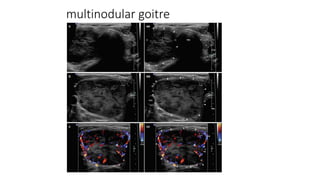

multinodular goitre

Multi nodular goiter

• Enlarged gland with

multiple cold, warm or

hot areas giving the

gland a coarse patchy

appearance.

• #71 Sonography is the first radiological investigation to screen the nodules and look for any suspicion of malignant change in the nodules which is not uncommon. Usually, the benign nodules in a multinodular goiter show the following features: iso-hyperechoic surrounding hypoechoic halo spongiform/honeycomb pattern peripheral (eggshell) or coarse calcifications

• #74 CT is not the diagnostic tool of choice, it however shows a large heterogeneously enlarged gland with multifocal solid nodules that suggest the diagnosis which is confimed by ultrasound and scintigraphy.